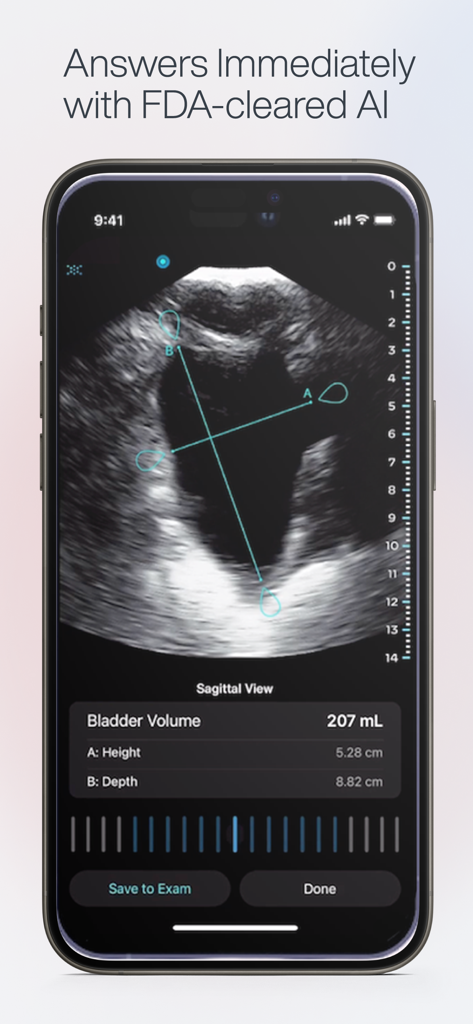

AI-Powered Clinical Insight

Achieve higher diagnostic confidence with real-time AI guidance that helps you capture the perfect window and automate complex measurements.